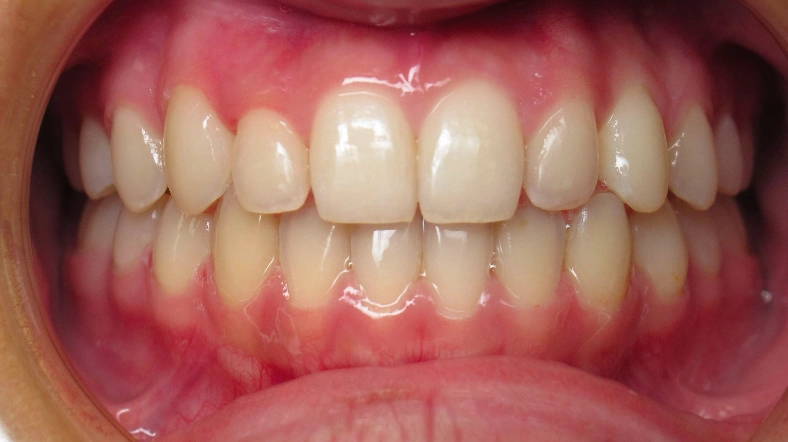

Underbite Before and After

After

Correcting an underbite improves jaw function and chewing efficiency while preventing abnormal tooth wear and potential jaw joint problems that can develop from the misaligned bite. Treatment also enhances facial aesthetics by balancing the profile and can improve speech clarity, while early intervention in children can guide proper jaw growth and prevent more severe skeletal discrepancies from developing. Correcting an underbite could be done with braces or invisalign. Severe cases may require a jaw surgery.